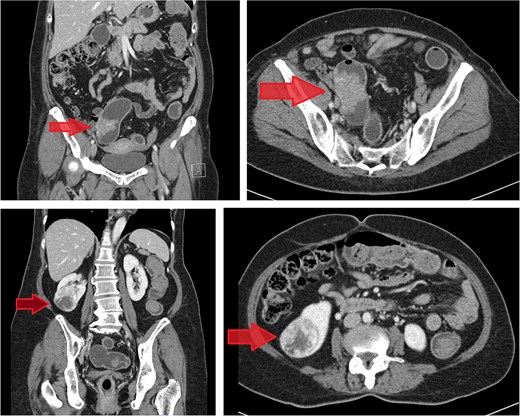

Computed tomography (CT) scan of the abdomen revealed a 5.2 mm polypoid lesion at the rectosigmoid colon without evidence of pericolonic fat extension, adjacent organ invasion, or regional/distant lymph node enlargement. Incidentally, a 5 cm hypervascular mass was noted at the lower pole of the right kidney, demonstrating peripheral enhancement with central low density. CT scan of the chest revealed no lymph node enlargement or pulmonary metastasis. On CT scan, the rectosigmoid colon mass exhibited radiologic characteristics suggestive of sigmoid colon cancer, while the lower pole right kidney mass demonstrated features consistent with RCC (Fig. 1).

Contrast-enhanced CT images of case 1. Top-left: Coronal view of the sigmoid colon cancer. Top-right: Transverse view of the CRC. Bottom-left: Coronal view of the renal cell carcinoma (RCC). Bottom-right: Transverse view of the RCC.